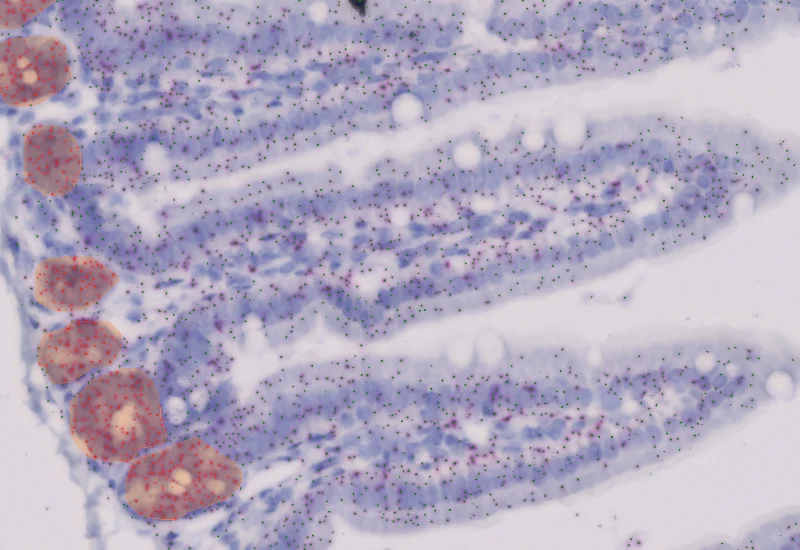

IHC Small Intestine - Dots

Segment nuclei and villi, detect single dot markers (CISH/RNAscope/SISH) in villi and manually defined crypts, and quantify dot count, area, intensity, and distribution per region.

The IHC Small Intestine - Dots App provides nuclei segmentation as well as detection of tissue and villi based on nuclei staining. crypts need to be defined manually. Furthermore it allows the dot detection for one dot markers (CISH, RNAScope, SISH) within villi and crypt area. Dot parameters are provided for villi and crypts and include count, mean intensity, total dot area, and sum of intensity as well as area and intensity lists for all single dots.

Image courtesy of Emma Nye, Head of Experimental Histopathology, The Francis Crick Institute, London, UK